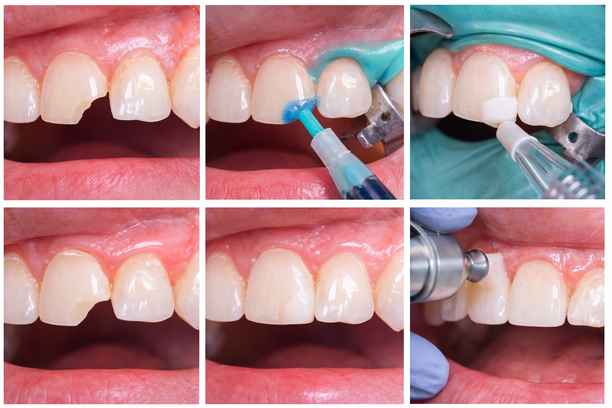

تسوس الأسنان الأمامية قبل وبعد

قبل الحشو، قد يظهر التسوس على شكل بقع داكنة أو ثقوب صغيرة تؤثر على مظهر السن ووظيفته.

بعد العلاج، يتم استعادة الشكل الطبيعي للسن باستخدام مواد تجميلية تحاكي لون الأسنان، مما يعيد التناسق للابتسامة ويمنع تفاقم المشكلة. وهنا يتجلى مفهوم حشو اسنان قبل وبعد في أوضح صوره، حيث يتحول السن من حالة ضعف إلى حالة استقرار وجمال.

حشوات تجميلية للاسنان قبل وبعد

تُظهر نتائج حشو اسنان قبل وبعد تحولاً ملحوظاً في مظهر الأسنان ووظيفتها، حيث يتم الانتقال من أسنان متضررة أو متصبغة إلى أسنان أكثر إشراقاً وتناسقاً، وهو ما يعكس جودة المواد المستخدمة ودقة التنفيذ داخل مركز أضواء الحكمة.

- قبل الحشو قد تعاني الأسنان من فراغات أو كسور أو تغير في اللون يؤثر على الابتسامة بشكل عام

- بعد الحشو يظهر تحسن واضح في الشكل العام مع استعادة التناسق بين الأسنان

- تزداد الثقة بالنفس نتيجة التحسن الجمالي الملحوظ الذي ينعكس على تعابير الوجه

- يتم تعزيز الوظيفة المضغية بشكل أفضل مما يساهم في راحة المريض أثناء الأكل .

كيف يتم عمل حشوة الأسنان الأمامية؟

تتم عملية الحشو وفق خطوات مدروسة تبدأ بالتشخيص وتنتهي بالتلميع النهائي للحصول على مظهر متكامل.

- تنظيف المنطقة المصابة من التسوس باستخدام أدوات دقيقة لإزالة الأنسجة التالفة

- تحضير سطح السن بطريقة تضمن التصاق المادة بشكل فعال

- وضع مادة الحشو وتشكيلها بعناية لتتناسب مع الشكل الطبيعي للسن

- استخدام أجهزة خاصة لتثبيت المادة وتصلبها بشكل نهائي

- إجراء التلميع النهائي لضمان نعومة السطح وانسجام اللون مع بقية الأسنان .